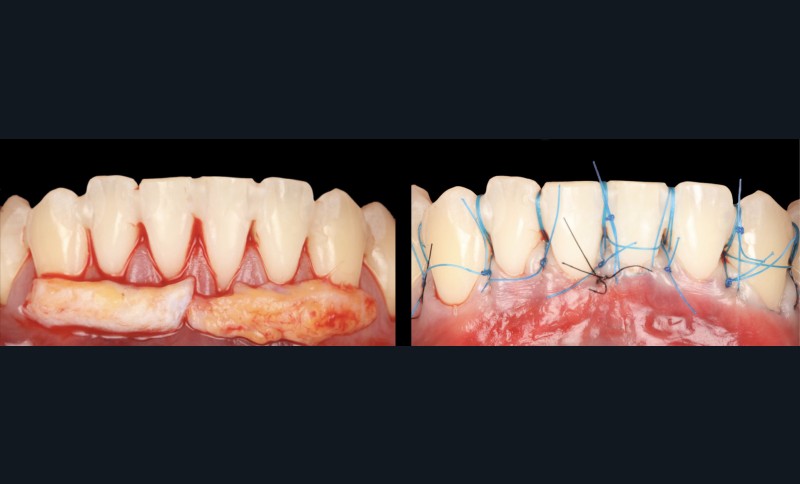

La stratégie chirurgicale, fondée sur les arbres décisionnels de Stefanini (2018) [4] et Aroca (2025) [5] a conduit au choix de la technique du tunnel modifié (MCAT) avec greffon de tissu conjonctif (CTG). Trois interventions successives furent réalisées (secteurs 33-43, 33-36, 43-46), avec positionnement du CTG à la jonction émail-cément et avancement coronaire des tissus (fig. 2 et 3).